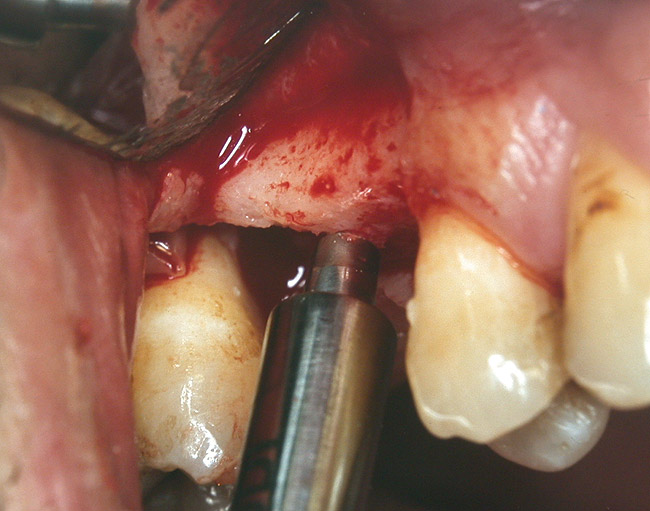

At the time of surgery, the tooth was extracted without harvesting any mucosal flap because the implant site was prepared by means of a pilot drill bur (Figure 13) and alternating osteotomes (Figure 14A and Figure 14B). The implant was positioned and showed primary stability. The implant was loaded 2 days after surgery. Then, splinted PFM crowns supported by custom gold abutments were delivered. At 6 months posttreatment, the radiograph revealed no bone resorption and the clinical result was optimal (Figure 15A and Figure 15B).

Figure 14a  Alternating osteotomes were used to prepare the implant site.

Figure 14a

Figure 14b  Alternating osteotomes were used to prepare the implant site.

Figure 14b